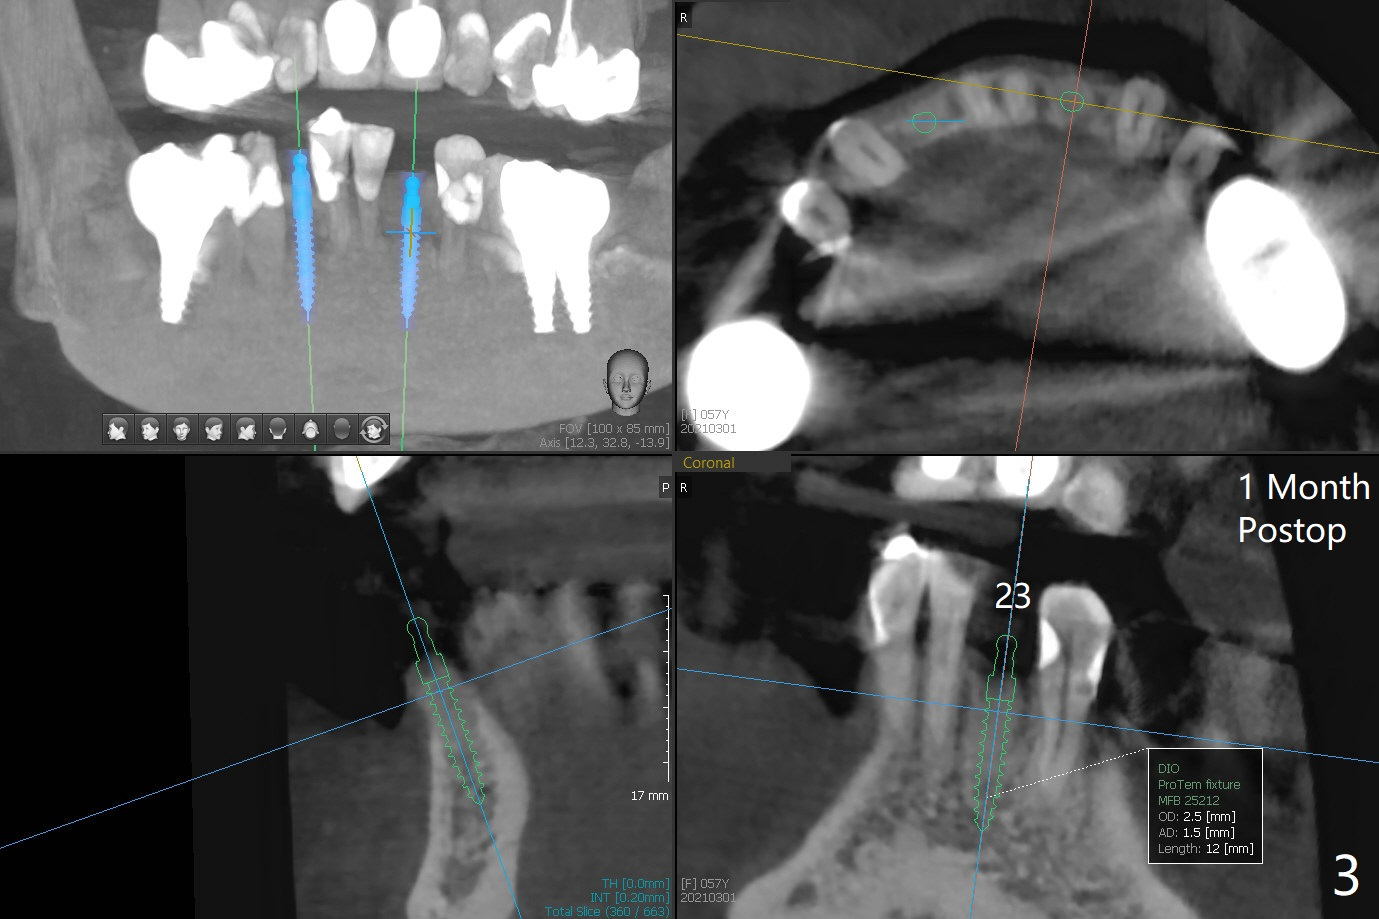

57岁女,口干症,前一个月(23,29号牙),三个月(26号牙)拔除植骨,可能需要再等一个月(出差)才能手术,会不会太早植牙?骨质还不够

植骨后2-3个月会不会太早植牙?